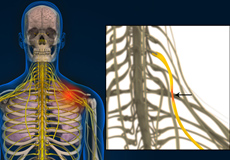

Arm Pain of Spinal Origin

Arm pain of spinal origin can be described as discomfort or pain felt anywhere in the arm including the wrist, elbow, or shoulder as a result of a pinched nerve (nerve compression) or irritated nerve in the spinal cord. The pain can occur as a dull constant pain or a sudden sharp pain that can develop suddenly or over time. The pain may be confined to one area of the arm or may radiate to other areas of the arm such as the hand, wrist, elbow, or shoulder.

Peripheral Nerve Compression

The human body has 2 nervous systems, the central nervous system that includes the brain and spinal cord, and the peripheral nervous system that includes a network of nerves that lie outside the brain and spinal cord.

Radiculopathy

Radiculopathy is a condition where a nerve root in the spine is compressed, producing pain or weakness across the whole length of the nerve. It is sometimes referred to as a pinched nerve or sciatica. It occurs most commonly, but is not limited, to the lower back and neck.